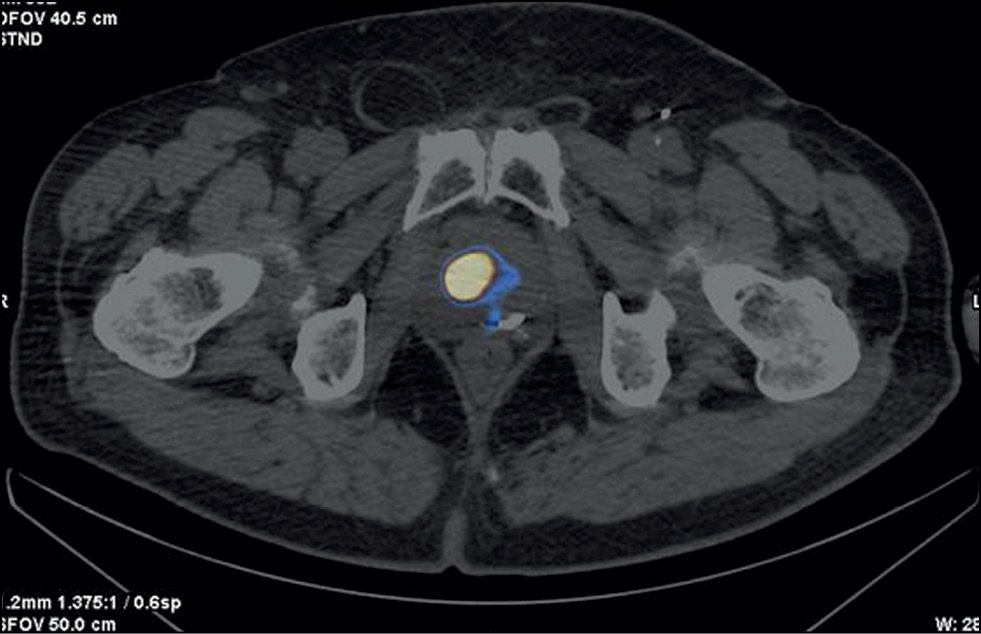

Figure 2 shows SPECT/CT data with 99mTc-HYNIC-PSMA.

Fig. 2. Patient Zh., 8 years old, SPECT/CT with 99mTc-HYNIC-PSMA, axial projection: Site of radiopharmaceutical accumulation in the transition zone of the middle part of the right prostate lobe.